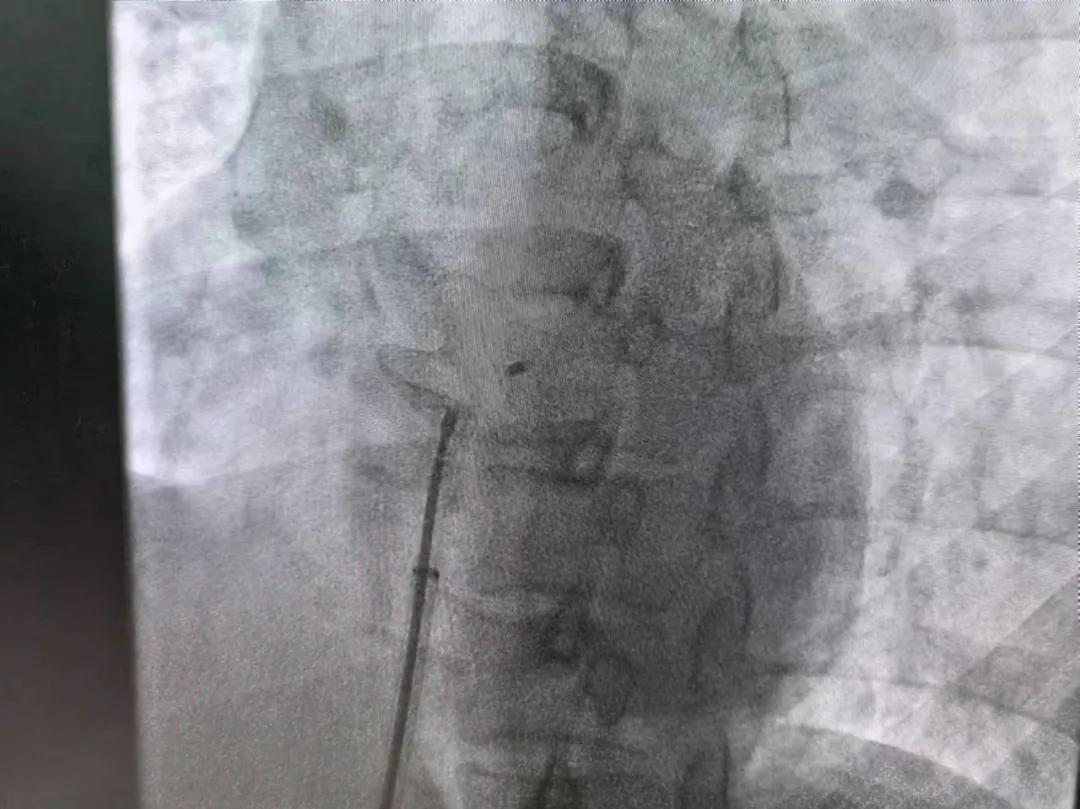

繼3月14日市二院成功開展首例卵圓孔未閉介入封堵術之后,3月21日上午,市二院院長王瑾及心血管內科主任李慧新帶領心血管內科介入團隊,再次成功為患者實施“經皮房間隔缺損封堵術”,手術過程順利。該例病人的成功手術及康復,標志著市二院心血管內科在結構性心臟病介入診療中再次達到了新高度。

患者為中年女性,41歲,近2年一直反復出現(xiàn)頭暈、頭痛,曾先后在多家醫(yī)院就診。近期患者癥狀加重,出現(xiàn)活動后氣喘合并胸悶癥狀,來到心血管內科就診。經心臟彩超檢查顯示:患者房間隔下段連續(xù)性中斷,缺損直徑達到了13mm,肺動脈壓已經輕度增高,確診為房間隔缺損。

于是,院長王瑾會診后,詳細詢問患者病史,認真分析臨床癥候群并準確診斷,耐心做好患者及家屬病情告知和充分溝通。經過完善的術前評估及準備,心血管內科介入團隊成功為患者實施“經皮房間隔缺損封堵術”,手術過程順利。近日,患者已順利康復出院。 (尹紅婭 潘長林)